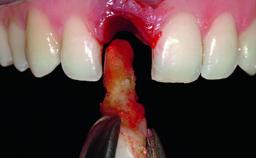

A healthy 37-year-old female patient was referred for a consultation on the replacement of missing tooth 21 with an implant-supported restoration. She stated that several years previously the tooth had been traumatically avulsed following a motor vehicle accident. The tooth was replaced with a three-unit fixed partial denture (FPD) immediately afterwards. Over time, she became disillusioned with the FPD and looked for a different option, including orthodontic therapy. She presented still in her orthodontic appliances, with the pontic sectioned free from the FPD but attached to the archwire. Her orthodontist felt that orthodontic treatment had been successfully completed, but nevertheless referred her before removing the appliances in case adjustments were necessary.

| Bone Augmentation | Horizontal|Simultaneous |

| Augmentation Materials | Xenogenous|Membrane |

| Soft Tissue Grafting | Simultaneous |